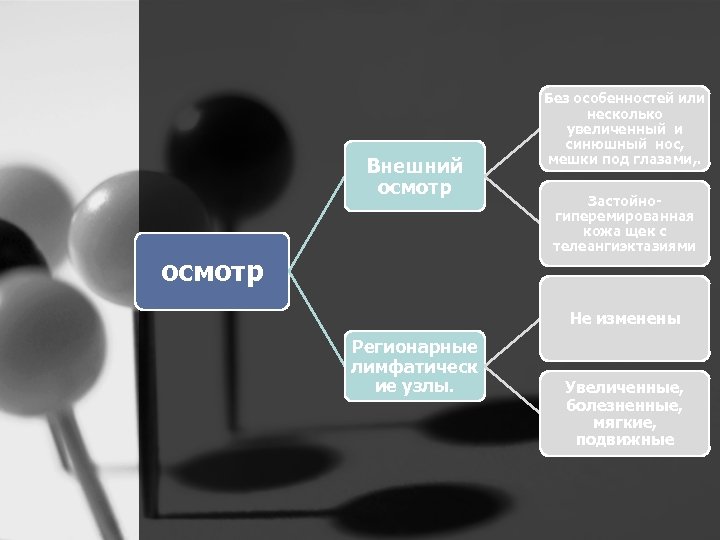

Внешний осмотр Без особенностей или несколько увеличенный и синюшный нос, мешки под глазами, . Застойно гиперемированная кожа щек с телеангиэктазиями Не изменены Регионарные лимфатическ ие узлы. Увеличенные, болезненные, мягкие, подвижные